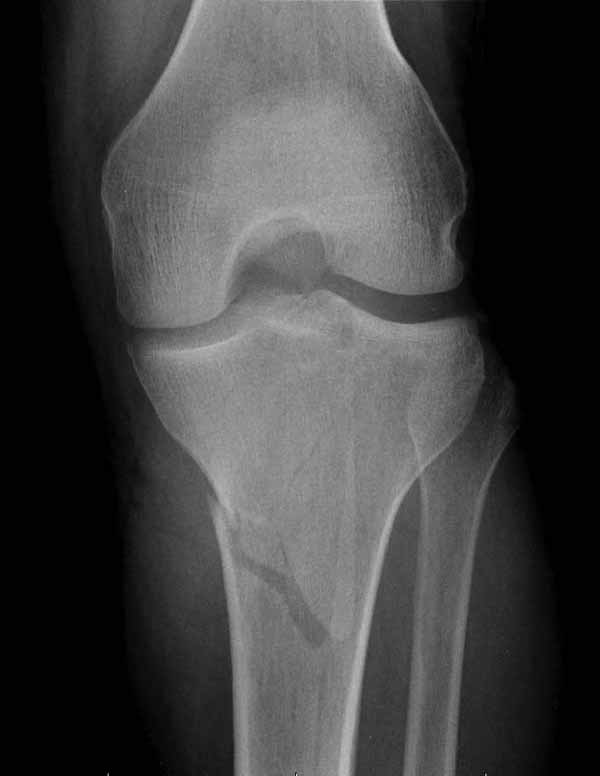

Двухколоннный перелом тибиал плато с вовлечением проксимального диафиза. Внутрисуставной компонент без смещения, и такой перелом можно лечить любым из описанных методов, о которых говорят наши коллеги.

Удобно аппаратом Илизарова или интрамедуллярным гвоздем. Гвозди не так сложно, как пугают, тем более Александр готов помощь с методичкой. Сперва надо установить компрессирующие шурупы на мыщелки. Давно отказались в пользу 3.5-4.0 мм кортикальных вместо толстых спонгиозных, потому что не доказаны преимущества толстых шурупов. Тонкие шурупы в субхондральной зоне смотрятся намного элегантнее, чем толстые 6.5.

Это мероприятие превращает перелом в простой диафизарный, который легко можно фиксировать гвоздем. Шурупы надо установить сзади предполагаемого места введения гвоздя.

Как понял, аппарат Илизарова не рассматривается предпочтительным для фиксации методом, хотя на фоне отека было бы идеальным для данного перелома. Для пластины требуется идеальная кожа, иначе наличие “суперсовременных имплантов” не поможет, и могут развиться серьезные осложнения.

Частая ошибка, когда фиксацию двух колонного перелома проводят одиночной пластиной, т.е с одной стороны, и такая фиксация не удерживает, происходит вторичноое смещение. Необходимо нейтрализовать второй пластиной или дополнительным наружным фиксатором.

Кстати, коллеги правы для уточнения характера перелома надо делать Компьютерную Томографию.